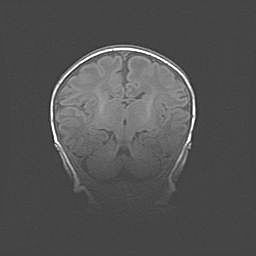

Наружная гидроцефалия с возможной атрофией височных областей.

Возраст: 28 дней

Вес: 3670 г

Пол: мужской

Окружность головы: 38 см

Срок гестации: 40 недель

Гидроцефалия головного мозга у новорожденных – это заболевание, которое характеризуется скоплением избыточного количества спинномозговой жидкости в желудочковой системе головного мозга в результате затруднения её перемещения от места выработки к месту поглощения в кровеносную систему или вследствие нарушения абсорбции. При открытой наружной форме гидроцефалии у новорожденных расширяются и переполняются субарахноидные пространства.

При нормотензивных  формах,  которые,  как  правило,  являются  следствием  перенесенных ишемических  повреждений  паренхимы  мозга,  возможно  сочетание микроцефалии  с нормотензивной гидроцефалией. В основе данных изменений лежит атрофия больших полушарий с преимущественной  локализацией  в  лобно-височных  областях.